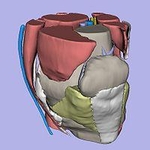

SPL Knee Atlas |

CT Atlas of the Abdomen Slicer4.4 09/2015 version |